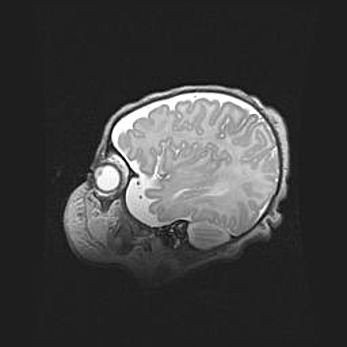

Мальформация Денди-Уокера. Киста задней черепной ямки.

Агенезия мозолистого тела.

Возраст: 2,5 месяца

Вес: 2420 г

Пол: женский

Окружность головы: 37 см

Срок гестации: 32 недели

Мальформация Денди—Уокера — редкий вид патологии ЦНС, представляющий собой врожденный порок развития каудального отдела ствола и червя мозжечка, ведущий к неполному раскрытию срединной (Мажанди) и латеральных (Лушка) апертур IV желудочка мозга. Для этогно синдрома характерна триада симптомов: гипотрофия червя мозжечка и/или полушарий мозжечка, кисты задней черепной ямки, гидроцефалия различной степени. В 70% случаев порок сочетается и с другими аномалиями головного мозга, в частности с агенезией мозолистого тела.